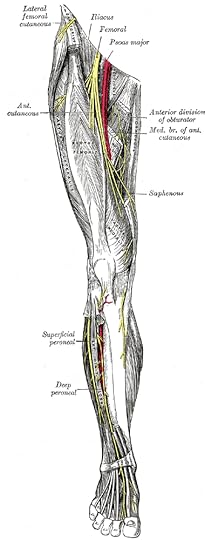

crural

cruralPRONUNCIATION:

(KROOR-uhl)

MEANING:

adjective: Relating to the leg.

ETYMOLOGY:

From Latin crus (leg). Earliest documented use: 1599.

USAGE:

"She could tell by his occasional grimace that her massage of his crural muscle above the patella on his right knee still caused him discomfort."

Kenneth Johnson; V: The Second Generation; Tor; 2008.